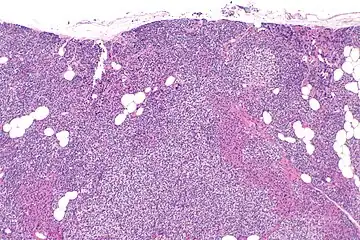

Parathyroid hyperplasia low mag. -

Parathyroid hyperplasia medium mag. -

Parathyroid hyperplasia high mag.

Primary hyperplasia of the parathyroid gland, results from both hypocalcaemia and increased phosphate levels by decreasing expression of calcium sensing receptors and vitamin D receptors at the parathyroid gland.[8][4] These decreases in receptor expression lead to hyperfunctioning of the parathyroid. Hyperfunction of the parathyroid gland is thought to exacerbate primary hyperplasia which evolves further to a secondary more aggressive hyperplasia. Histologically, these hyperplasic glands can be either diffuse or nodular.[24] Primary hyperplasia, usually resulting in diffuse polyclonal growth is manly related to reversible secondary hyperparathyroidism. Secondary hyperplasia of the parathyroid gland is more often a nodular, monoclonal growth that sustains secondary hyperparathyroidism and is the catalyst in the progression to tertiary hyperparathyroidism. Nodular hyperplastic glands in tertiary hyperparathyroidism are distinctly larger in both absolute size and weight up to 20-40-fold increases have been reported.[25][26][24]

Parathyroid glands are normally composed of chief cells, adipocytes and scattered oxyphil cells.[27][14] Chief cells are thought to be responsible for the production, storage and secretion of parathyroid hormone. These cells appear light and dark with a prominent Golgi body and endoplasmic reticulum. In electron micrographs, secretory vesicles can be seen in and around the Golgi and at the cell membrane. These cells also contain prominent cytoplasmic adipose.[27][14] Upon onset of hyperplasia these cells are described as having a nodular pattern with enlargement of protein synthesis machinery such as the endoplasmic reticulum and Golgi. Increased secretory vesicles are seen and decreased intercellular fat is characteristic.[27][24] Oxyphil cells also appear hyperplasic however, these cells are much less prominent.